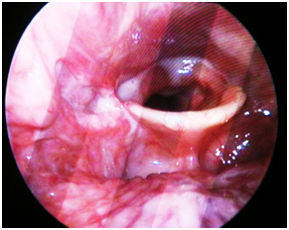

A 52year old male patient with dysphagia, sore throat, hemoptysis, cough and neck swelling referred to emergency department. He had diabetes mellitus and underwent dental filling ten days before. Physical examination revealed a swelling on the anterior pharyngeal wall. In videolaryngoscopic examination a fistula orifice and purulent discharge on the right pyriform sinus was observed (Figure 2). Neck magnetic resonance imaging (MRI) planned with retropharyngeal abscess diagnosis (Figure 3). Due to spontaneous drainage surgical intervention was not considered.

Figure 2 Drainage orifice on the right pyriform sinus, purulent drainage tot the larynx.

Figure 3 Neck MRI findings.